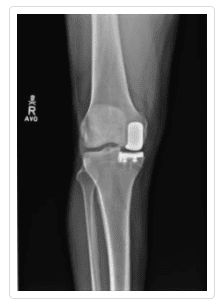

If nonsurgical treatments are not enough, you will need to have surgery. As with nonsurgical options, the purpose of surgery is to reduce pain, increase function, and generally, reduce your symptoms. Patient satisfaction is a fundamental goal in treating arthritis of the knee. There are a number of options available, including cartilage grafting, arthroscopic surgery, total or partial knee arthroplasty, and osteotomy.

Knee Arthritis Gallery

To see more examples of knees with arthritis, please visit our knee x-ray gallery.